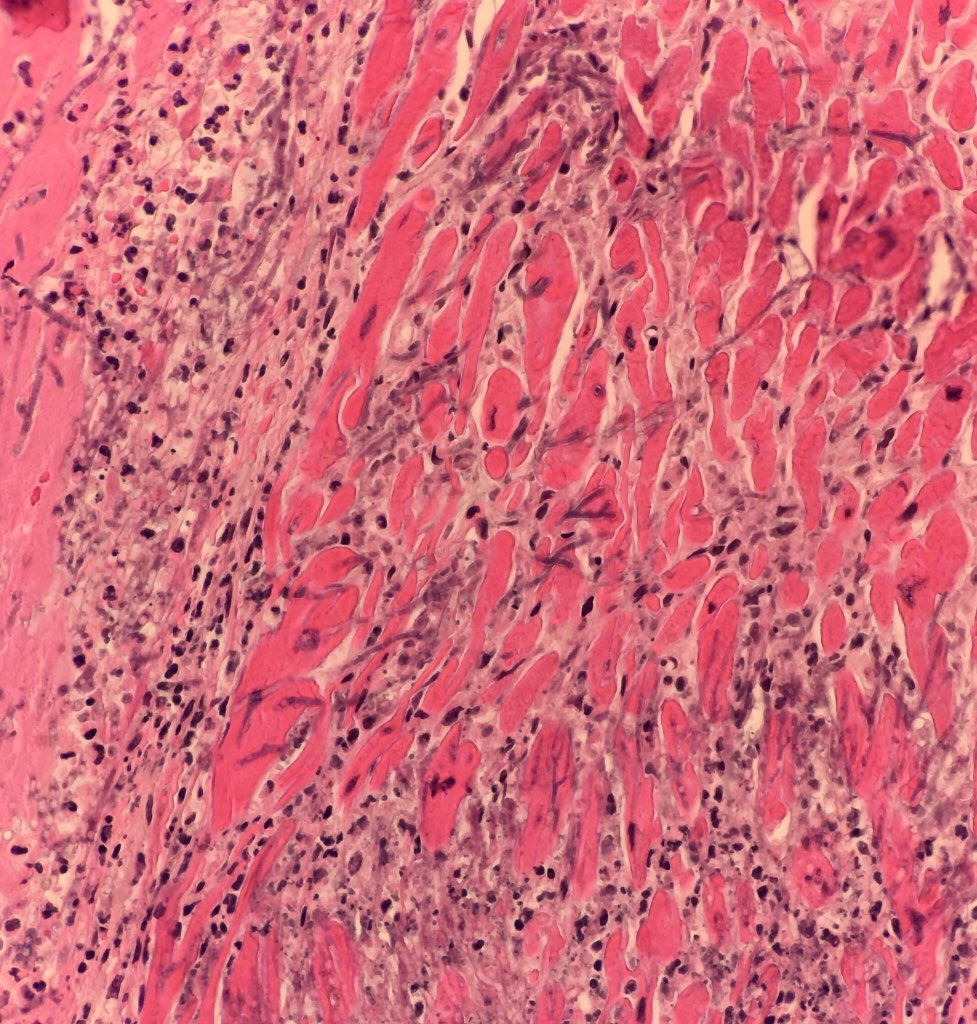

Межуточный миокардит: гистологические исследования